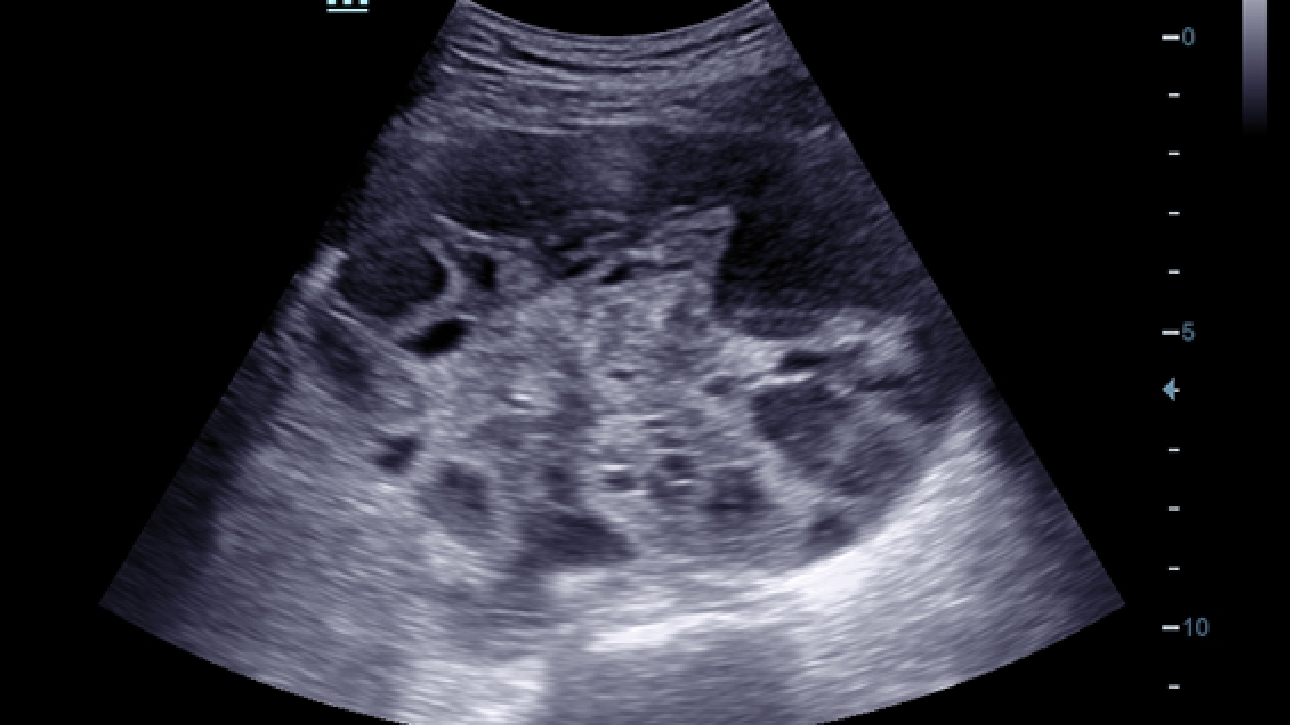

De DC-60 Exp met X-Insight is ontworpen op basis van diepgaand inzicht in klantbehoeften om hoge effici?ntie met nauwkeurige beeldverwerking te leveren, dankzij eXacte helderheid, eXceptionele intelligentie en eXcellente ervaring.